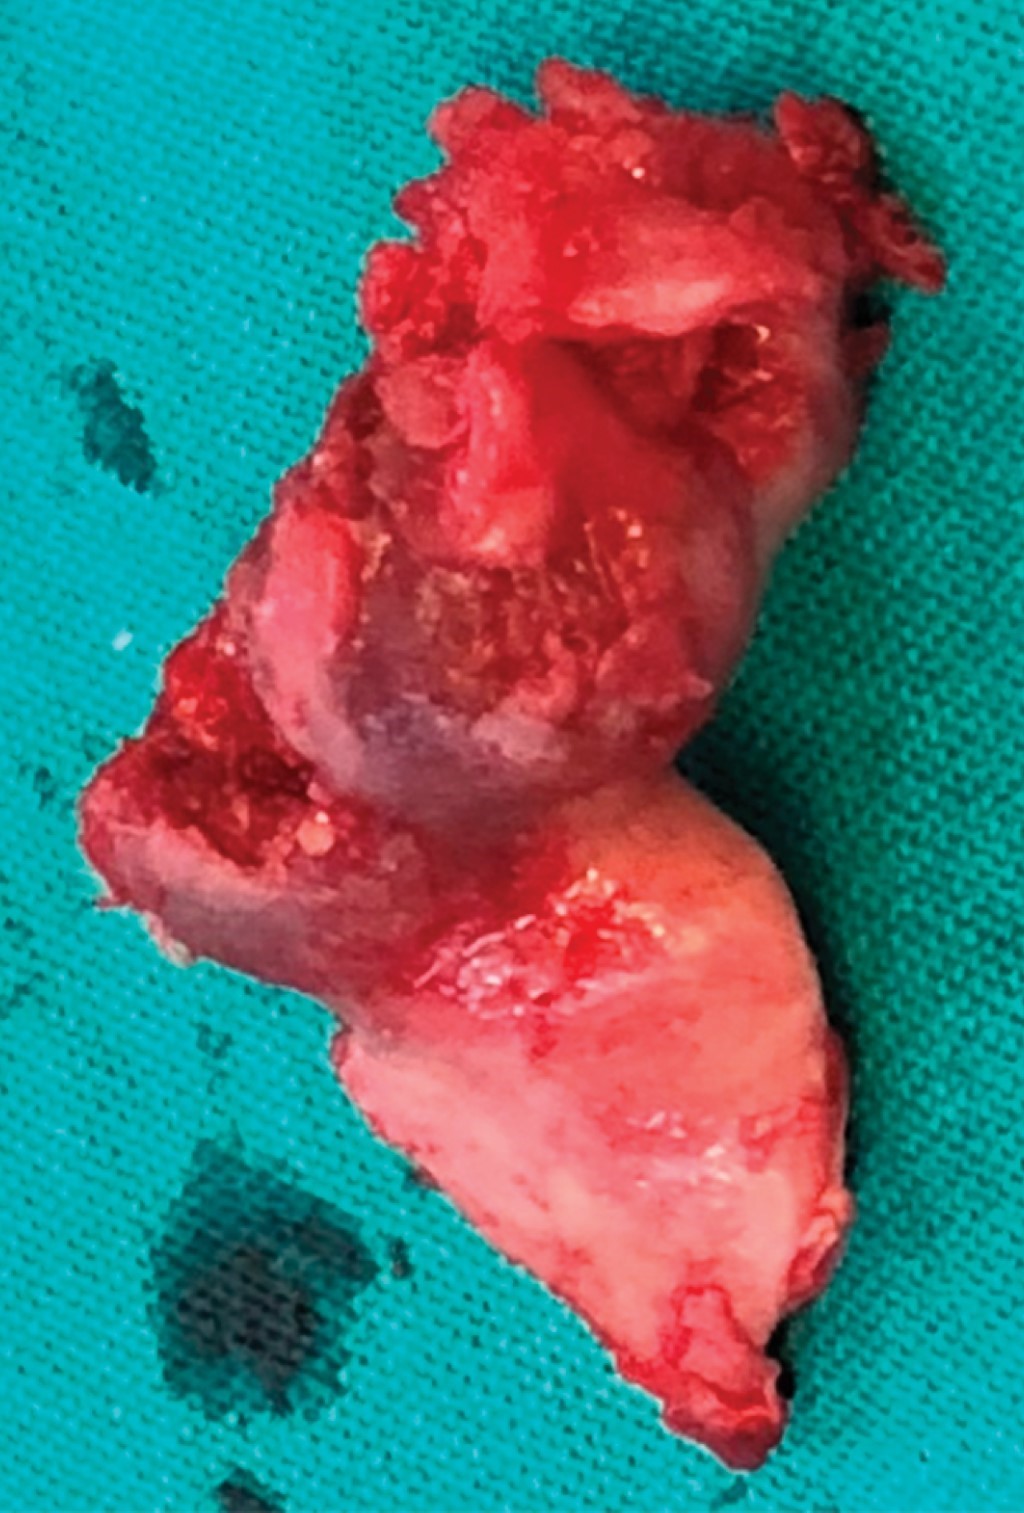

Se realiza tratamiento quirúrgico bajo anestesia general con intubación nasotraqueal y por medio de abordaje intraoral se procedió a la coronoidectomía con instrumental rotatorio, desinserción del músculo temporal y remoción de una masa tumoral con forma de hongo envuelta con un tejido cartilaginoso (Figuras 8 y 9).

El estudio histopatológico informó un fragmento óseo de 2.5 × 5.5 cm que presenta una formación exofítica grisácea firme con superficie externa irregular. Los cortes histológicos muestran tejido cartilaginoso típico superficial con formación ósea trabecular subyacente típica con escasos focos cartilaginosos intratrabeculares. Diagnóstico osteocondroma (Figura 10).